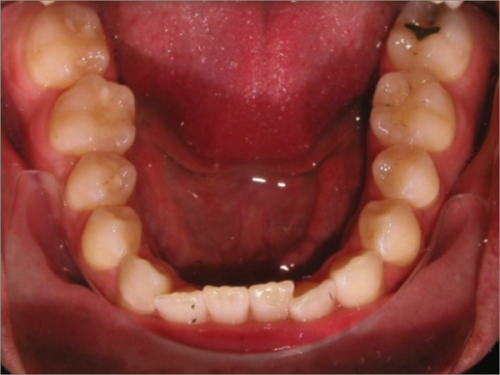

30 year old male:

Diagnosis:

- Upper and lower crowding

- Narrow upper & lowerarch forms

- Open bite

Treatment:

- Invisalign

- Non-Extraction

- 27 months